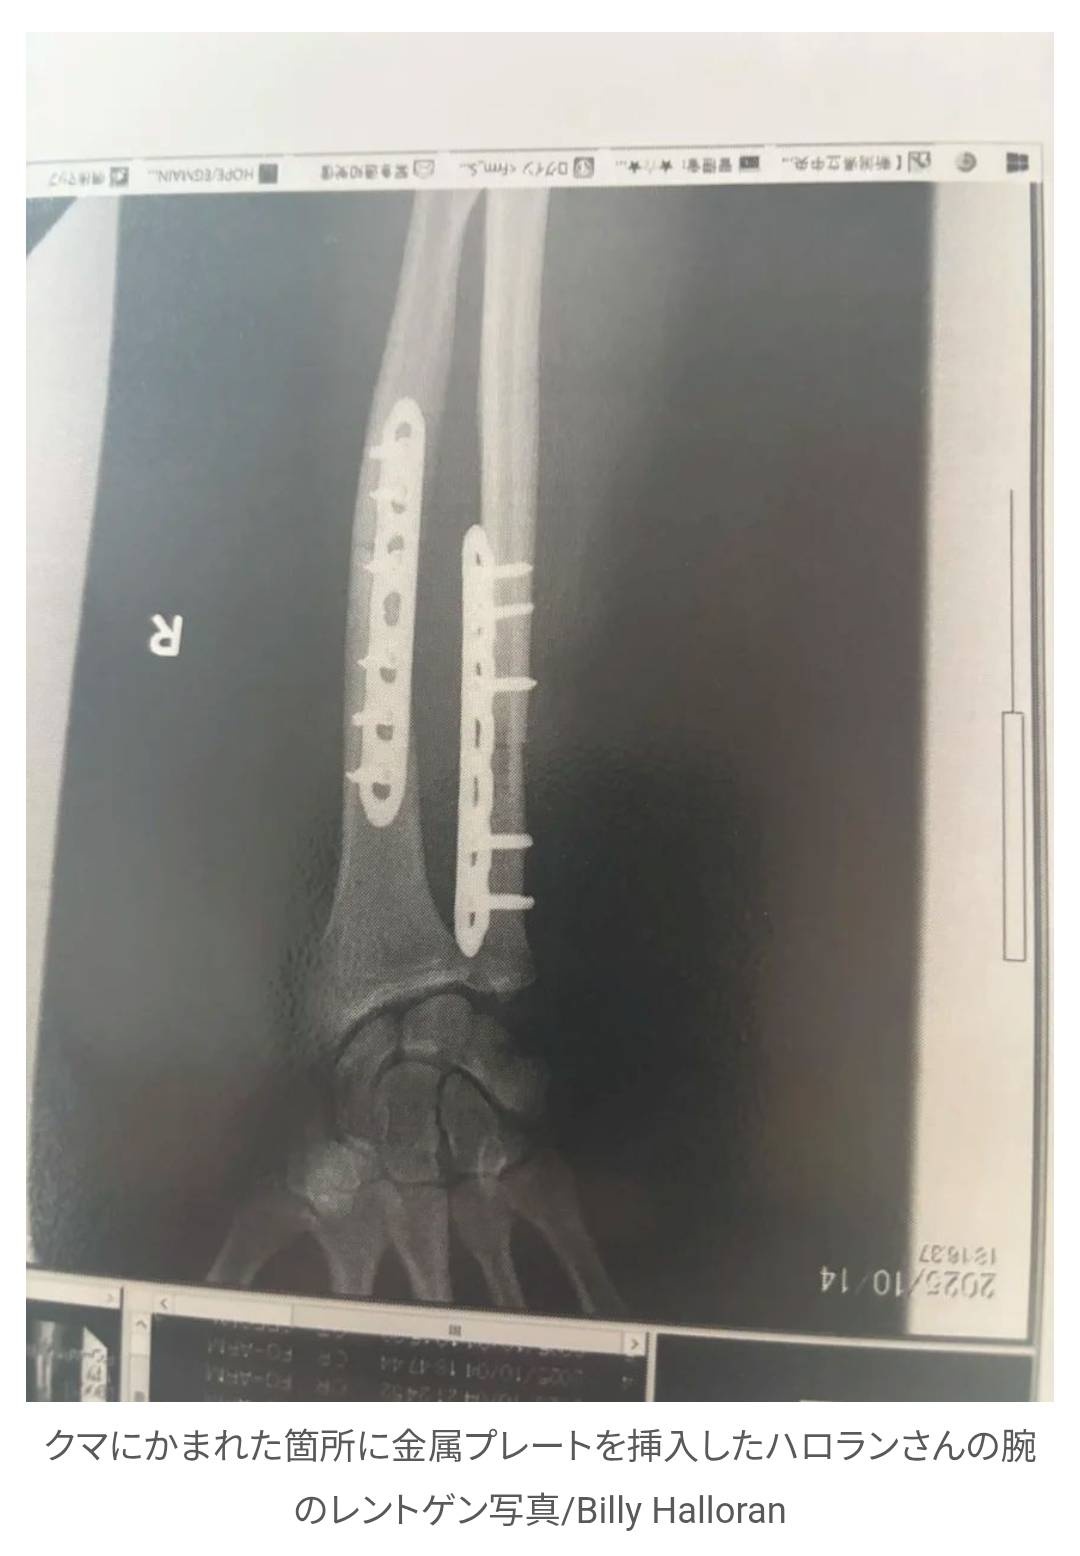

この2週間、ハロランさんは病院で療養している。負傷した腕への金属プレート挿入を含む3度の手術を受けた後、CNNの取材に応じた。